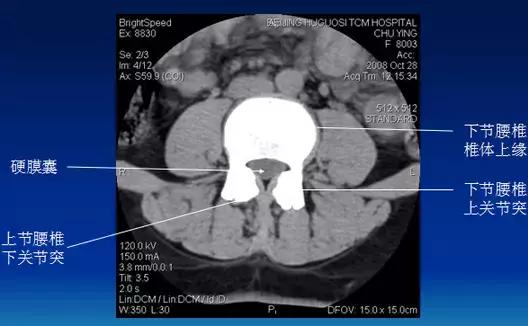

常规腰椎CT扫描层面

常规腰椎CT扫描L3-S1段,分为

(1)椎体层面(骨窗):观察椎体、附件骨质。

(2)椎间盘层面(软组织窗):观察椎间盘、硬膜囊、神经根、韧带等软组织。